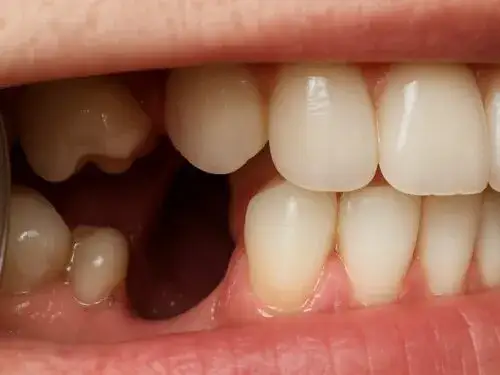

Co oznacza "ruchomy ząb" u dorosłego i kiedy jest to objaw raka?

Zazwyczaj rozchwianie zębów u osób dorosłych jest związane z chorobami przyzębia. Jednak jeśli zauważysz, że Twój ząb staje się nagle ruchomy bez wyraźnej przyczyny periodontologicznej, a zwłaszcza jeśli towarzyszą temu inne objawy, takie jak ból czy obrzęk dziąsła, warto skonsultować to ze stomatologiem. W rzadkich przypadkach może to być związane z naciekaniem kości przez nowotwór.